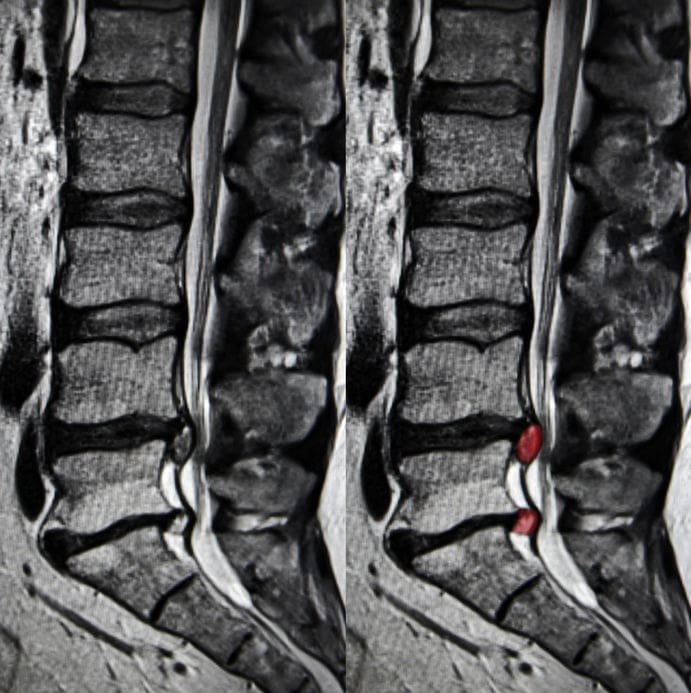

МРТ позвоночника лучше визуализирует грыжу и соседние мягкие ткани, поэтому врачу по ее результатам легче поставить точный диагноз и принять решение о необходимости хирургического или медикаментозного лечения.

Что лучше — КТ или МРТ пояснично-крестцового отдела позвоночника?

Если причиной обращения в диагностический центр является боль в пояснице, то следует сделать МРТ пояснично-крестцового отдела позвоночника, поскольку она покажет изменения как в костных, так и мягких тканях. Если у вас уже есть первичный диагноз, то решение о том, КТ или МРТ пояснично-крестцового отдела позвоночника нужно делать, должен принять лечащий врач на основе собранного анамнеза.